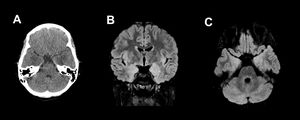

Twenty-year-old male, hospitalised for fever and progressive alteration of level of consciousness. Initial MRI (A) showed areas of increased signal intensity on T2/FLAIR in the periventricular and subcortical white matter which were attributed to chronic ischaemic microangiopathy. In a follow-up magnetic resonance imaging performed 13 days later (B and C), these findings had disappeared, but there were new foci of oedema in the left thalmus and cerebellum. Involvement of the mesencephalic substantia nigra was also seen on T2-weighted (D) and T2/FLAIR (E) sequences. This patient’s clinical condition was extremely serious and unfortunately he died.